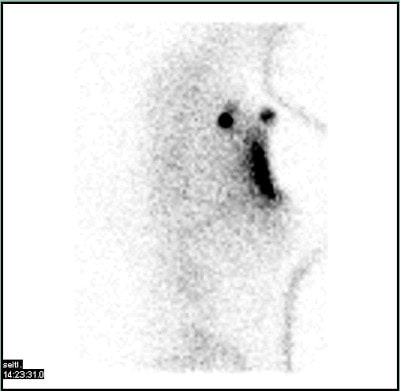

Die Sentinellymphknoten-Szintigraphie betrifft den oder die Wächterlymphknoten, also den oder die Lymphknoten, die einem Tumor unmittelbar nachgeschaltet sind.

Nach Darstellung und Markierung des oder der Wächterlymphknoten werden diese chirurgisch entfernt und feingeweblich untersucht. Abhängig von einem evtl. Tumorbefall des Wächterlymphknotens ergeben sich dann der Umfang der Tumoroperation und ggf. auch die Notwendigkeit einer zusätzlichen Bestrahlung und/oder Chemotherapie.

Die Sentinellymphknoten-Szintigraphie gehört heute zum Behandlungsstandard vieler Tumorerkrankungen, insbesondere auch bei Brust- und Prostata-Krebs.